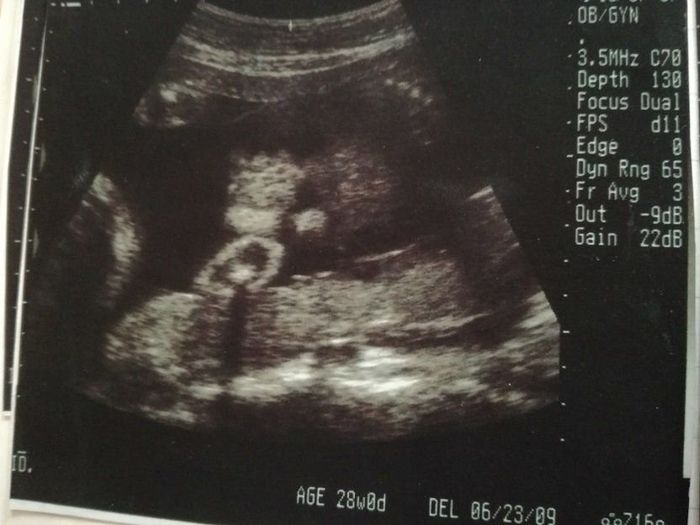

妊娠28週目のエコー写真

前回の検診で治ったと言われたはずなのに、またまた“逆子”になっていました。かなりアクロバティックに動き回っている様子。赤ちゃんが元気に動くことで、私のおなかも驚くほどによく変形しました。“逆子”になっていたこともあり、やはり性別は判明せず。先生からは、「次の検診で逆子が治っていなかったら、逆子体操をやってもらいますね」と言われました。